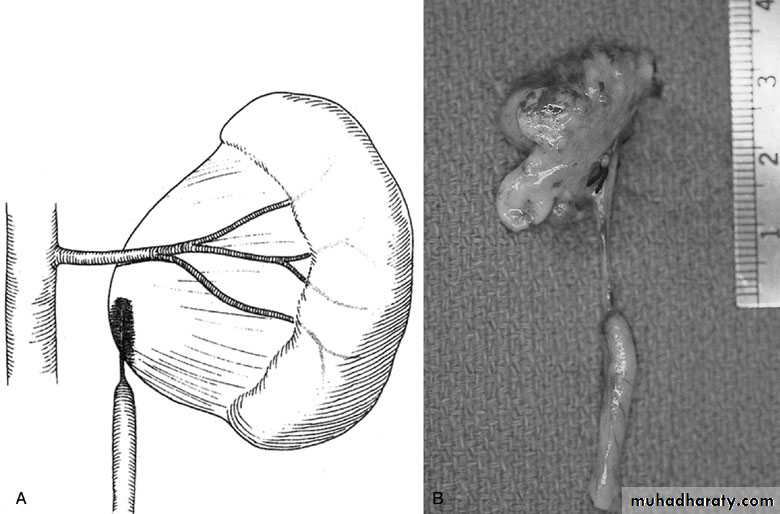

PUJ Obstruction – gross pathology

Open & laparoscopic surgical techniques Anderson-Hynes dismembered pyeloplasty:

excision of the pathologic UPJ & appropriate

reanastamosis or flap technique or flap

operation

Nephrectomy

for non functioning kidney